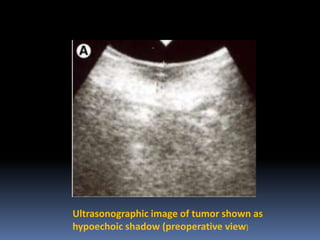

Intraoperative determination of tumor

thickness and resection margin in tongue

carcinomas using Ultrasonography

Ultrasonographic image of tumor shown as

hypoechoic shadow (preoperative view)

Intraoperative determination oftumor thickness and resection margin in tongue carcinomas using Ultrasonography

Ultrasonographic image oftumor shown as hypoechoic shadow (preoperative view)